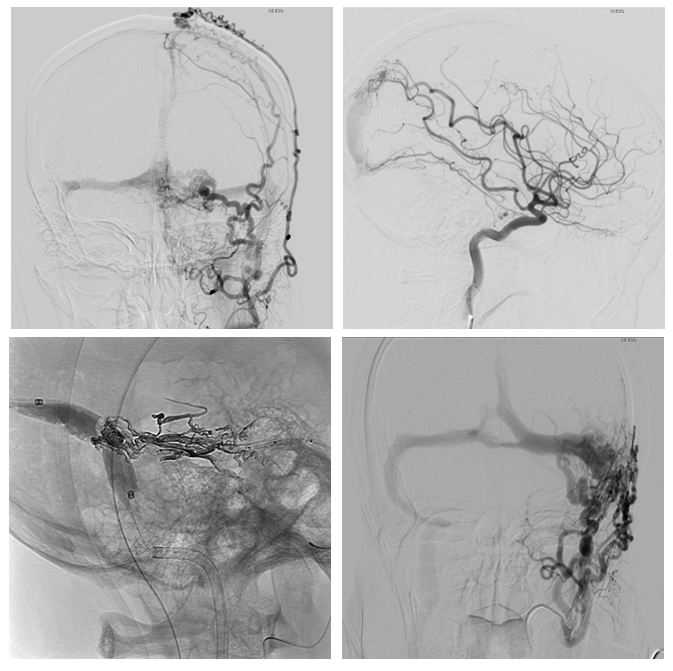

Dural Arteriovenous Fistulas - Regarding Two Clinical Cases

Cristiana Fernandes, Sara Varanda, José Manuel Amorim, José Nuno Alves, Carla Ferreira

International Journal of Innovative Research in Medical Science·August 1, 2021